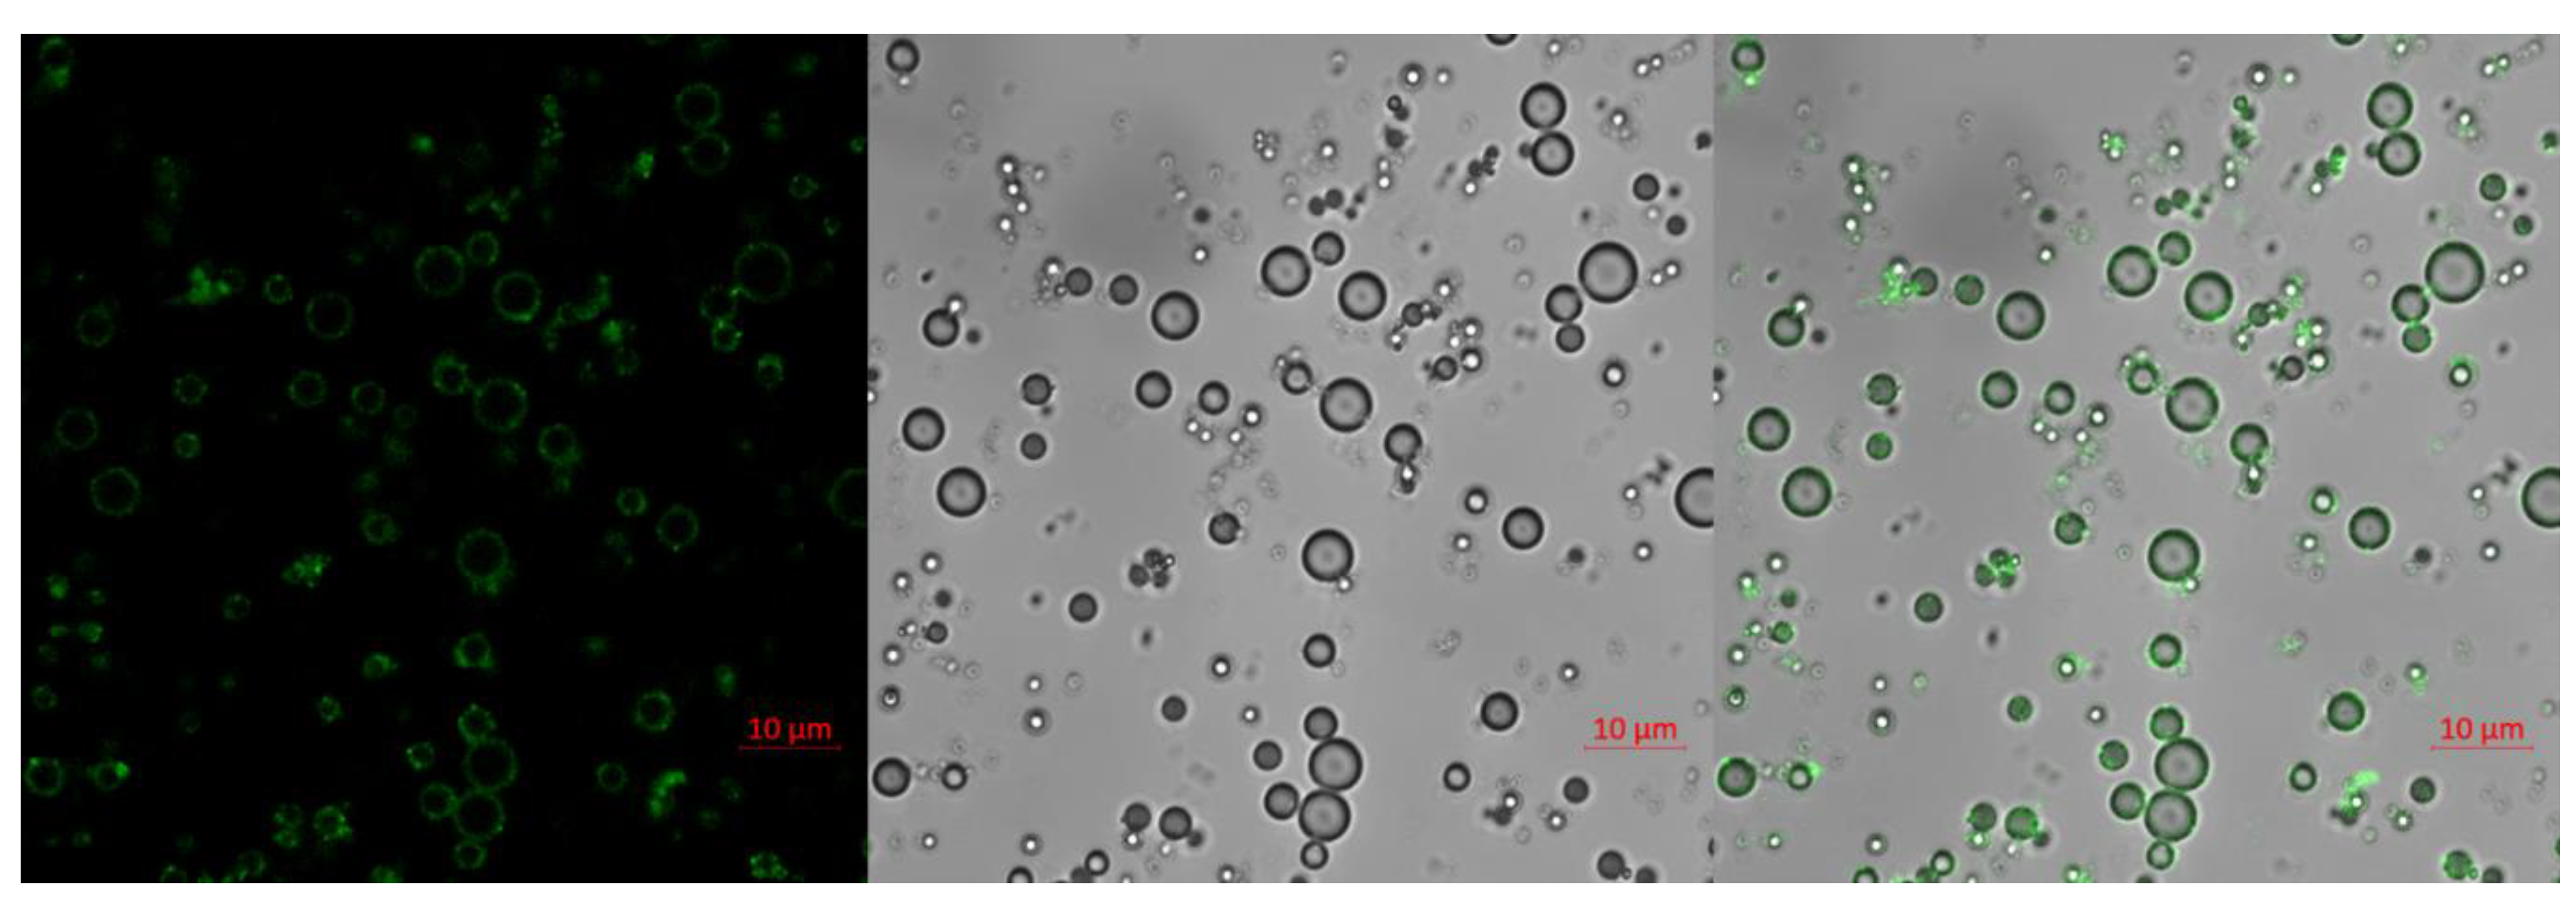

2.2. Confocal Image of IMC

4.4. Confocal Imaging